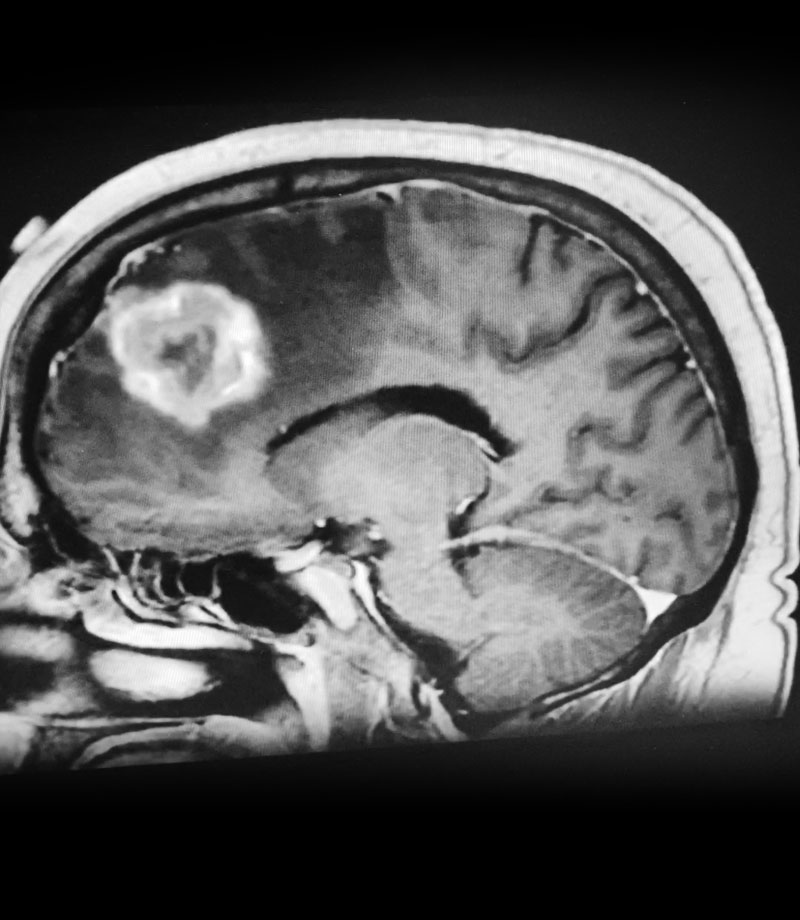

Figure 1: Sagittal post-contrast MRI.

The patient subsequently had increased headaches and weakness. MRI showed the mass had increased further, with persistent surrounding edema (Figure 1). Systemic work-up showed no active metastatic disease. It was suspected that there was recurrence of metastatic tumor as well as some component of necrosis (Figure 2). The patient underwent a right frontal craniotomy, by Dr. Michael Brisman, with brainlab stereotactic guidance. A cortical incision was made right over the mass. The mass was consistent primarily with metastatic tumor. The tumor was surgically removed.